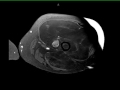

Well-differentiated Liposarcoma, Left Thigh

42-year-old male with gradually enlarging left thigh mass. Images demonstrate a multiseptated T1 hyperintense, STIR hypointense, heterogeneously enhancing mass enveloping the left femoral diaphysis and extending into the surrounding soft tissues. No periosteal reaction. There are enhancing, wispy, septations on the postcontrast images with more nodular excrescences at the inferior most aspect of the mass. On resection, this lesion was found to be a well-differentiated liposarcoma, which represents the second most common soft tissue sarcoma. Liposarcoma typically arise in adults between the ages of the 40 and 60 years. Typical locations include the extremities or retroperitoneum. Well-differentiated liposarcoma is the most common subtype, occurring in greater than 50% of cases. Extremity liposarcomas are typically slow growing and have variable rates of localized disease recurrence with deeper lesions more likely to recur. Primary surgical treatment is with wide local excision.